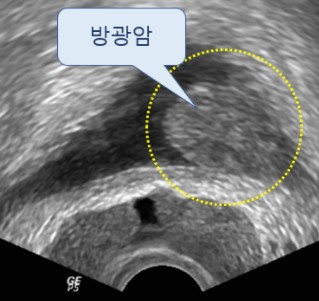

전립선암 원인, 초기증상 대해 알아보도록 하겠습니다., 전립선은 남자에게만 있는 장기로 정액의 일부를 생산하는 할 일을 해요. 전립선은 방광에서 나오는 요도를 둘러싸듯이 있으며 밤 열매와 같은 모양을 하고 있습니다. 전립선암은 이러한 전립선에 암세포가 발생을 한 것으로 50세 이후 60~70대에 많이 발생을 하는 남자만의 병입니다.

5. 요실금 및 수신증

요실금이란 자기도 모르는 사이에 소변이 나오는 증상입니다. 전립선암 초기증상으로 전립선에서 가장 가까운 방광 쪽으로 번질 그럴 때에 요실금 증상이 발생할 수도 있습니다. 또한 요관이 막히면서 소변이 방광으로 전달되지 못하고, 신장에 고이게 되는 그럴 경우를 수신증이라고 합니다.. 수신증의 그럴 경우 몸 뒤쪽인 등 부분에 고통이 생기는 것이 증상이라고 합니다.